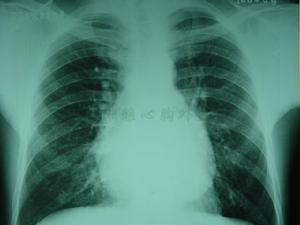

X線檢查:心包鈣化是曾患過急性心包炎的最可靠的X線徵象,在大多數縮窄性心包炎的患者中均可見到。常呈不完整的環狀。半數以上患者心影輕度擴大,其餘心影大小正常。心影增大與心包膜增厚,心包腔內殘餘積液、膈肌升高和心臟鄰近胸膜增厚有關。可表現為普遍性增大呈三角形或球形,心緣變直或形成異常心弓,如主動脈結縮短或隱蔽不見,左、右心房,右心室或肺動脈圓錐增大,上腔靜脈擴張。肺間影增大,肺血管充血,胸膜常增厚或有積液。X線透視或記波攝影可見心臟搏動減弱或消失。心血管造影能顯示各心腔的大小和在心動周期中形態的變化,從而估計心包的厚度和縮窄的程度。 計算機化X線斷層顯像對心包增厚具有相當高的特異性和解析度,若心包壁層只增厚0.5~2cm,圖像曲線呈現緻密組織現象,可提示增厚。磁共振顯像可分辨心包增厚以及有無縮窄存在。